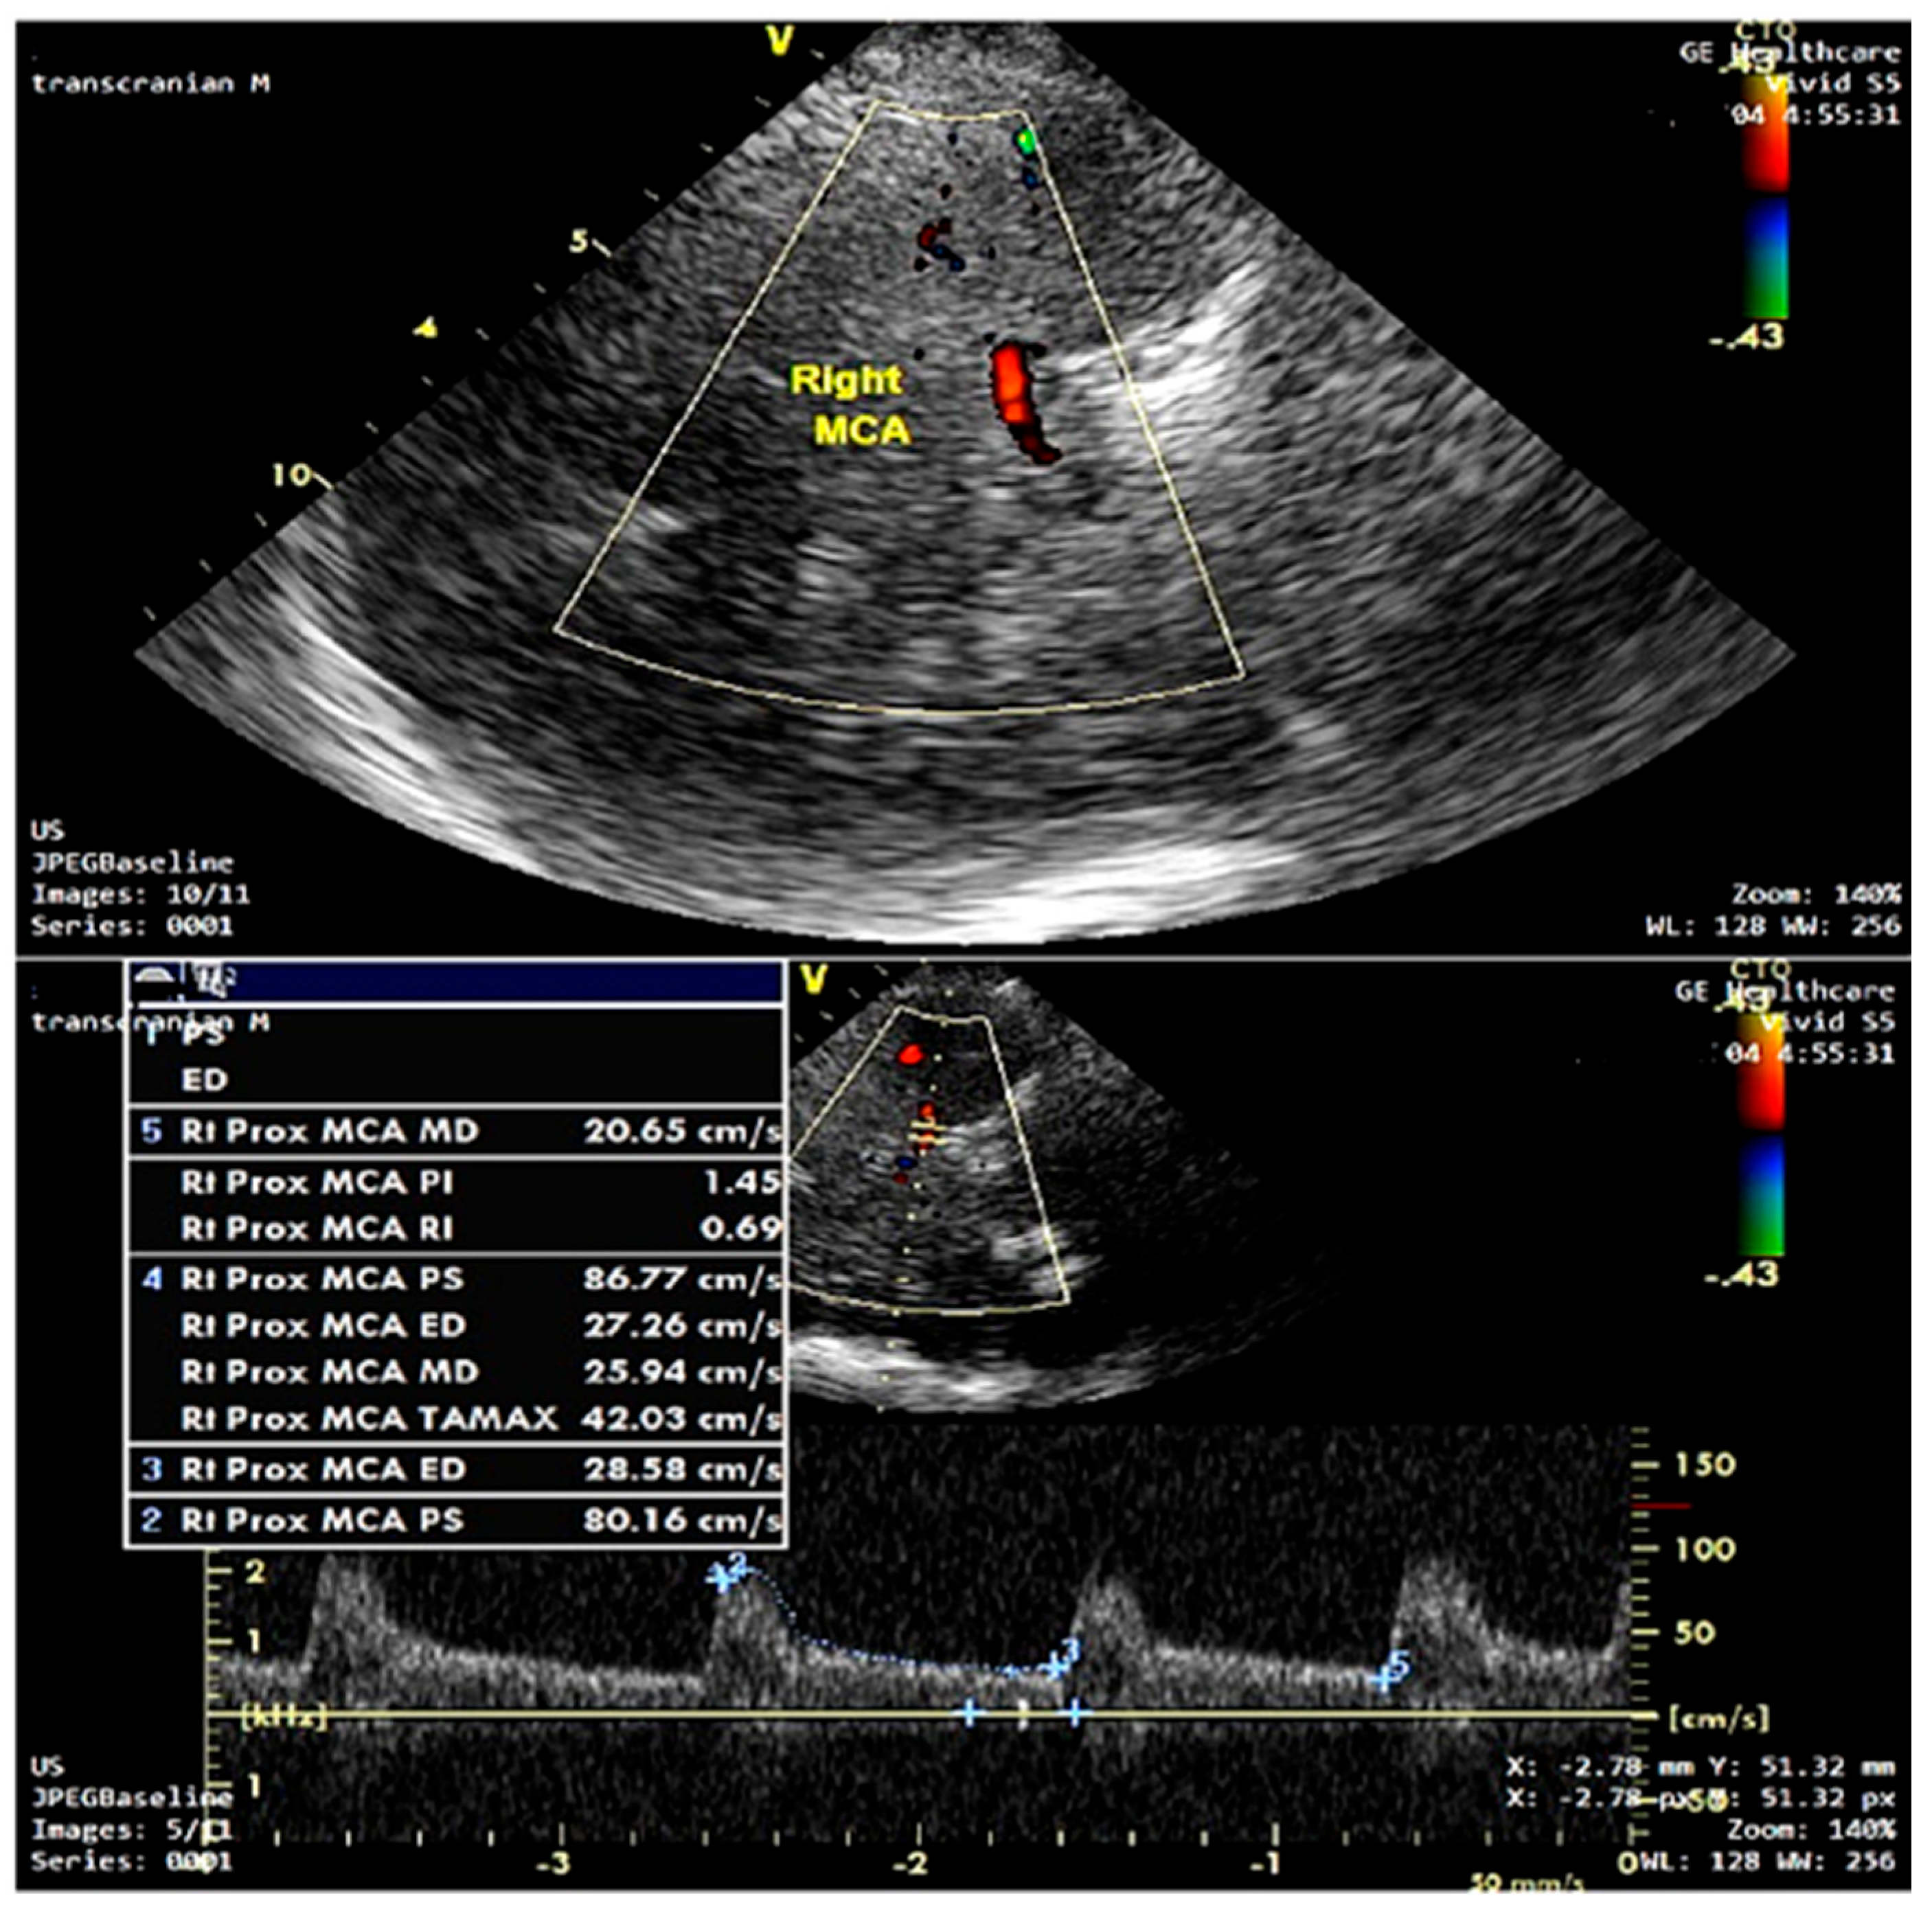

| TCD parameters | ||||

| Mean BFV | 56.3 (53.6–62.5) | 51.6 (50.8–52.6) | 56.3 (53.6–62.5) | <0.001 |

| PI (%) median (I–III quartile) | 0.73 (0.66–0.81) | 0.94 (0.91–0.96) | 0.73 (0.66–0.81) | <0.001 |

| RI (%) median (I–III quartile) | 0.51 (0.45–0.54) | 0.58 (0.55–0.65) | 0.51 (0.45–0.54) | 0.002 |

| PSV (cm/s) median (I–III quartile) | 84.95 (83.82–85.89) | 86.4 (84.9–88.6) | 84.9 (84.02–86.32) | 0.15 |

| EDV (cm/s) median (I–III quartile) | 40.65 (38.07–42.82) | 36.3 (33.4–39.3) | 39.9 (36.91–42.67) | 0.04 |